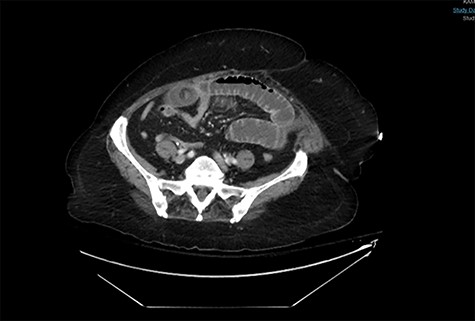

An 81-year-old woman with long history of gallstones was presented to the emergency department with persistent vomiting associated with progressive abdominal distension and inability to pass bowel motion or gases for the past 3 days. Examination showed stable vitals and distended abdomen. A computerized tomography (CT) scan showed high-grade small bowel obstruction in mid-ileum caused by a large impacted gallstone (Fig. 1). There was also a wide neck cholecystoduodenal fistula (Fig. 2).

A CT abdomen and pelvis scan showing a large stone in the small bowel.